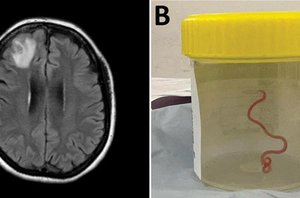

Atlikus pilvo kompiuterinės tomografijos (KT) tyrimą nebuvo jokių uždegimo ar infekcijos ženklų, tačiau gydytojai atsargumo sumetimais skyrė pacientei antibiotikų.

Po penkių valandų pilvo skausmas ligoninėje tapo toks stiprus, kad gydytojai atliko dar vieną KT tyrimą. Šį kartą paaiškėjo, kad ten, kur plonoji žarna jungiasi su storąja žarna, buvo uždegimas, todėl pacientė paguldyta į intensyviosios terapijos skyrių.

Tačiau po kelių dienų simptomai grįžo. Dėl pilvo skausmo ir viduriavimo moteris vėl kreipėsi į medikus. Naujas KT tyrimas parodė, kad storojoje žarnoje atsirado skylutės. Tai audinių žūtis, kuri mediciniškai vadinama nekroziniu enterokolitu.